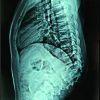

Her inflammatory markers remained elevated with worsening proximal weakness (power 3/5 over upper limbs and 2 to 3/5 over lower limbs) and a new onset of unrelenting back pain with cervicothoracic tenderness. A magnetic resonance imaging (MRI) study of the full spine found SEAs at levels C3/4, C6-7, T5 to T7, L1 to S2 levels, with central canal narrowing and severe cord compression by a large degenerative osteochondral bar at C5/6 with focal cystic gliosis. There was associated severe thecal sac and cauda equina compression from L2-3 to L4-5 levels. The T5 to T7 collections displayed mild indentation with no significant compression of the spinal cord. There was C3/4 and C6/7 infective spondylodiscitis and osteomyelitis, septic arthritis of left C3/4 and C4/5 facet joints, T5 and T6 costovertebral joint septic arthritis and osteomyelitis, bilateral loculated iliopsoas abscesses at L5 level and a right thigh abscess.

(Fig. 1, 2, 3) A computer tomographic (CT) scan of the thorax, abdomen and pelvis demonstrated a left pectoralis major abscess and left strap muscle abscesses, left sternoclavicular, and first sternocostal joint septic arthritis. A transthoracic cardiac echogram did not demonstrate any vegetations suggestive of infective endocarditis while a detailed head-to-toe examination did not reveal any obvious skin or dental lesions. The urinary analysis and urinary culture were unremarkable although the patient was also found to have chronic left obstructive hydronephrosis. The patient had no history of IV drug abuse. A multidisciplinary team comprising of specialists from internal medicine, cardiology, infectious diseases, anesthesia, otolaryngology, cardiothoracic surgery, urology, orthopedic, and spine surgery was assembled for pre-operative medical optimization. They also developed joint goals of surgery as well as a detailed surgical plan on the day of surgery and post-operative care. The patient underwent concurrent drainage of the left pectoralis major and left strap muscle abscesses, followed by C3/4, C5/6 anterior cervical discectomy and fusion (Fig. 4) in a supine position. The patient was subsequently turned prone for the drainage of lumbar SEAs with right L2/3, left L3/4, laminotomy, L5 and S1 laminectomy. The alternate-sided laminotomies were performed to preserve the contralateral structures to maintain spinal stability. Finally, the right psoas and right thigh abscesses were drained in a left lateral position. The thoracic SEAs and left psoas abscess were left undrained. The septic arthritis of left C3/4, C4/5 facet joints, T5/6, T6/7 costovertebral and left sternoclavicular, and first sternocostal joint was also conservatively managed.